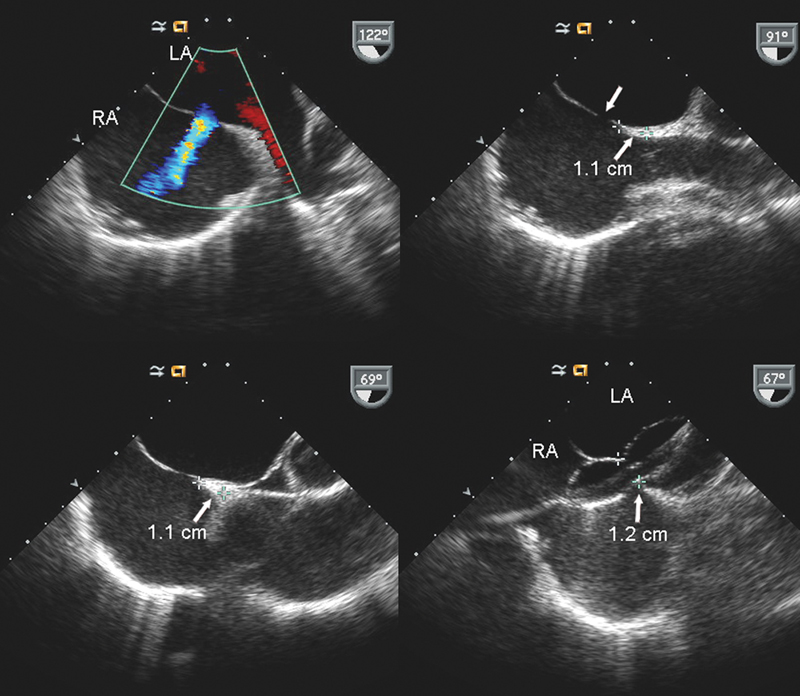

فحوصات تشخيصية لبعض امراض القلب والشرايين التاجية